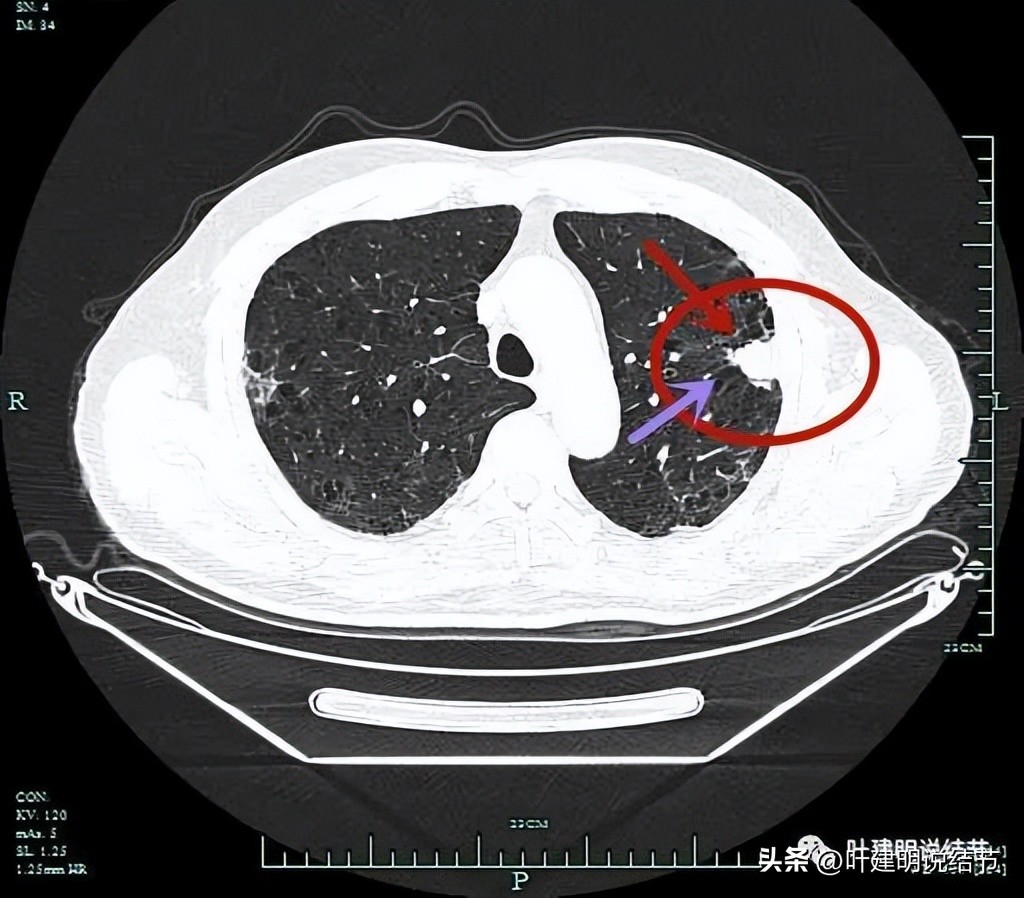

分叶征(砖色箭头);毛刺征(紫色箭头);胸膜牵拉(蓝色箭头);病灶有膨胀感(红色箭头)。

上图层面明显明显的收缩力、分叶、胸膜牵拉以及血管进入(桔色箭头)。

病灶实性,有纠集感;有胸膜牵拉;有毛刺征;有血管征。